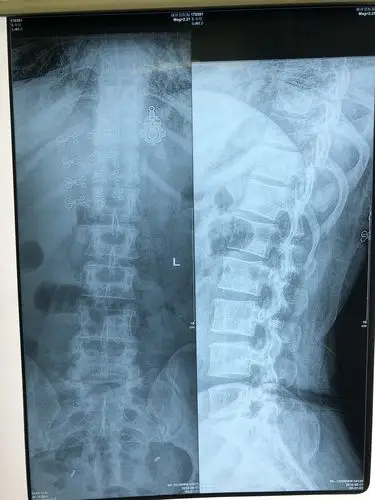

腰椎间盘突出微创手术第八天

腰椎间盘突出症的症状,检查及治疗_腰椎间盘突出_症状表现_检查_治疗

腰椎间盘突出微创治疗术中症状消失! - 好大夫在线

腰椎间盘突出腰疼